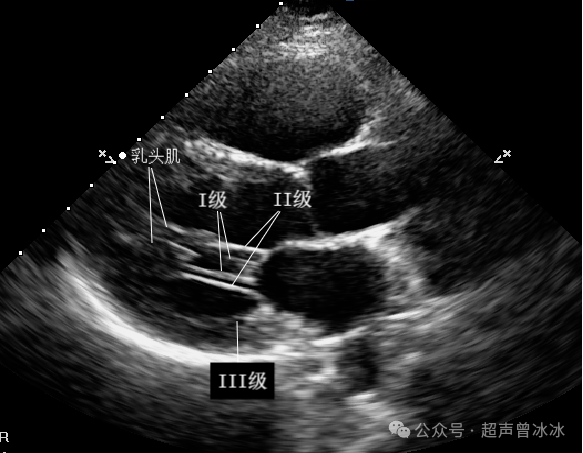

I级腱索:起自乳头肌,远端附着于瓣叶边缘,主要防止瓣叶边缘外翻。

II级腱索:起自乳头肌,附着于瓣叶中部,加强对瓣叶的牵拉作用。

III级腱索:发自左室壁,附着于瓣叶基底部,固定瓣膜位置的作用,只位于后叶。

对应到超声图像就是↓

2379d9bb5cb76627c2bfa05e449e24dc3f9fd0cdb70bf77f97d7b58eed1f3ea0a5628596df3061a4

其中,I、II级腱索是腱索的核心成员,断了、冗长了容易引起二尖瓣关闭不全、脱垂甚至连枷。

III型腱索既细又短,切断III型腱索不影响瓣膜的功能。